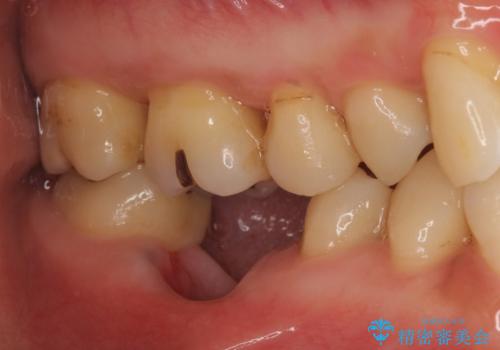

被せ物を外したところ、歯が大変薄くなって割れており、残念ながら残すことはできないと説明しました。

歯がなくなったところに関しては、ブリッジで修復することにしました。

初めての根の治療には見えないくらい、かなり歯が削ってあり、薄くなっていて割れても仕方ない状態でした。前の状態を見ていないので何とも言い難いですが、他の歯に比べこの歯だけ極端に状態が悪かったです。

当院は最後まで歯を残せるように、きちんと破折していないかチェックし、患者様に写真を確認していただいたうえで抜歯をするかを相談していきます。